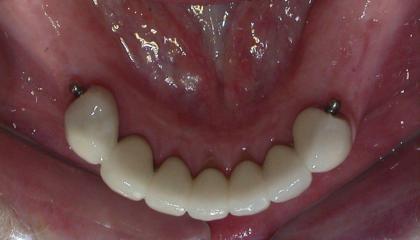

After

Zirconia bridge on Southern DC Implants